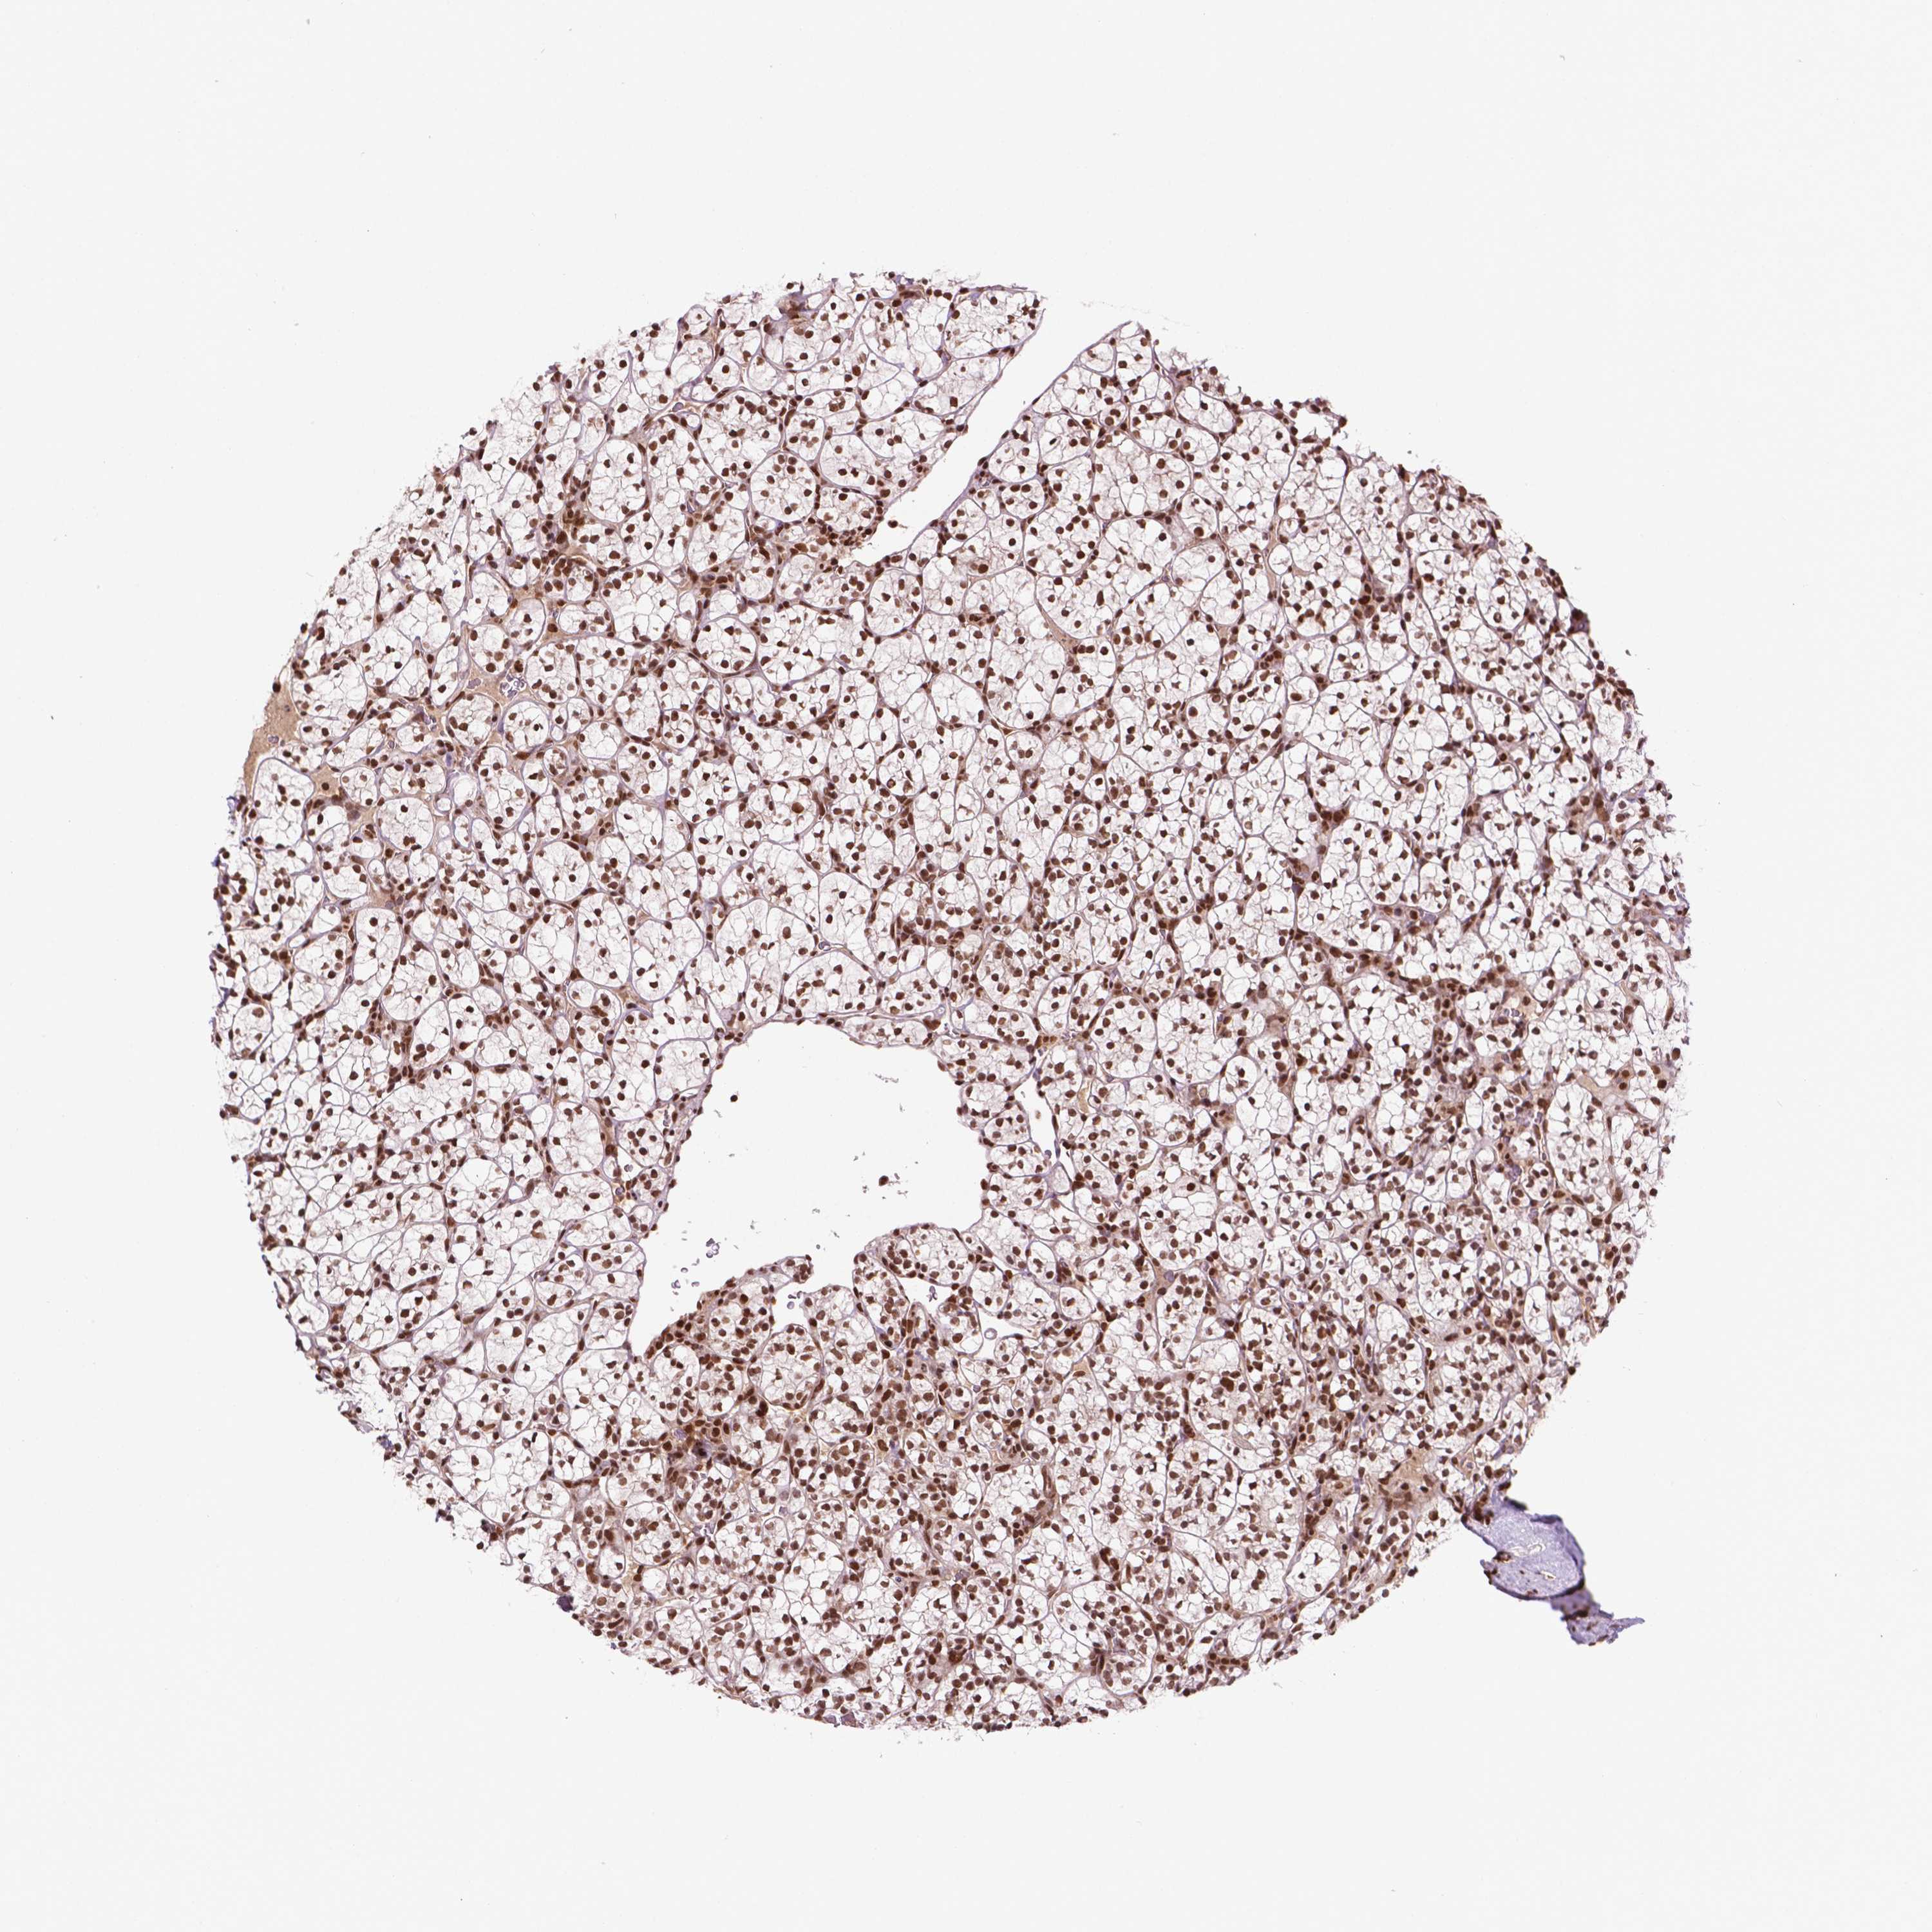

KIDNEY RENAL CLEAR CELL CARCINOMA (VALIDATION) - Interactive survival scatter ploti

SIRT6 is not prognostic in Kidney Renal Clear Cell Carcinoma (validation)

: 16.17

Average pTPM 13.4

Number of samples 100